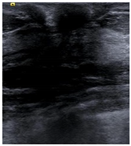

| Negative | Image | ![]() | ![]() | ![]() | ![]() |

| Number | 98 | 112 | 345 | 289 | |

| Positive | Image | ![]() | ![]() | ![]() | ![]() |

| Number | 47 | 49 | 161 | 184 | |